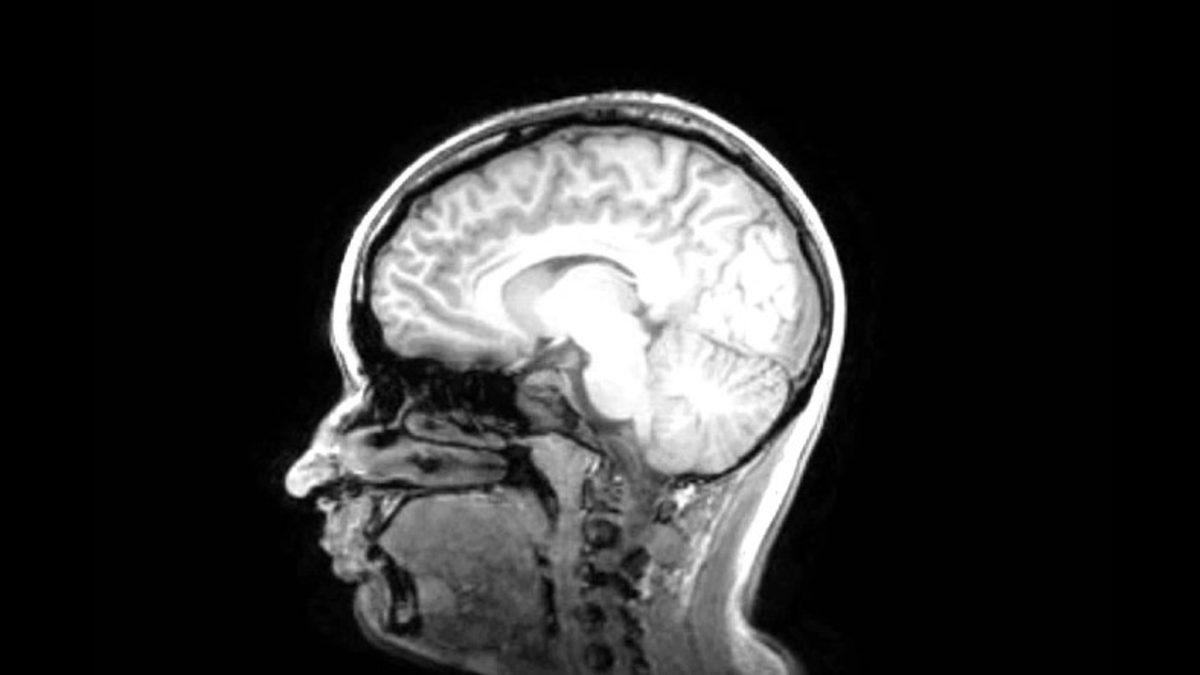

“Ölüm nihai bir son mu?” sorusuna cevap arayan bilim insanları, 4 saat önce mezbahada kesilmiş bir domuzun beynini laboratuvar ortamında makinelere bağlayarak beyin hücrelerini geri döndürmeye çalıştı.

Yapay besinleri beynin ağlarına iletebilmek adına BrainEx adlı bir sistem geliştiren araştırmacılar, uzun uğraşlar sonucunda beyin hücrelerinden sinyal almayı başarabildi. Ancak bu sinyaller, beynin yaşayan bir beyin olduğunu göstermekten çok uzaktaydı. Araştırmanın baş yazarlarından Zvonimir Vrselja, yayınlanan makalede elde edilen sinyallerin beynin yaşadığını değil, sadece hücresel olarak yeniden aktif olabildiğini gösterdiğini vurguladı.

Yani ölü domuzun beyninden alınan sinyaller, yaşayan bir domuzun aksine herhangi bir şey hissedemez ve düşünemez haldeydi. Domuzu dış görünüşünden ziyade domuz yapan bilinci, sinyal alınmasına rağmen orada değildi.

Vrselja, bu çalışmanın ölü bir canlıyı geri hayata döndürme yolunda bir ışık tutmasından ziyade, daha çok beyin ölümünün aşamalarını anlamak için işine yaradıklarını belirtiyor.